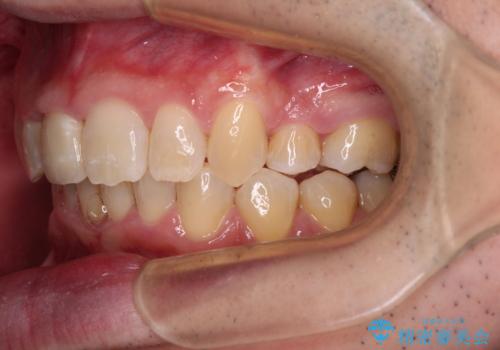

- ぶつけて前歯が折れてしまったとのことで来院された患者様です。

折れてしまった前歯は軽傷であり、歯内の歯髄に影響は及んでいませんでした。

通常では速やかにオールセラミッククラウンにて補綴治療を行うのですが、デコボコしている歯列も気になっていたため、事前に矯正治療を行うこととしました。